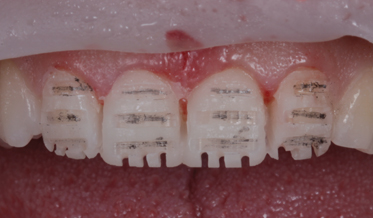

The Complete Digital Workflow in Implant Dentistry